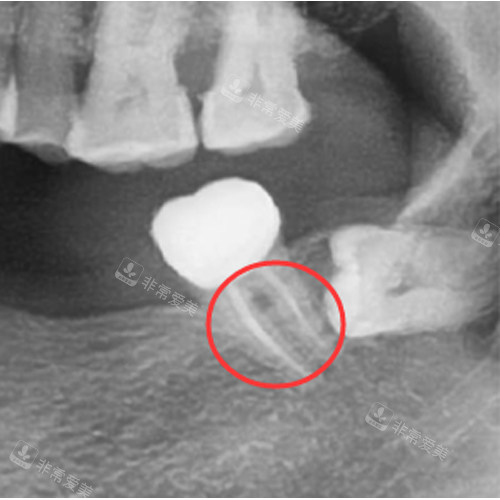

根管显微镜:德贝口腔配备了靠前的根管显微镜,它能让医生更清晰地观察根管内部的情况,大大提高了根管治疗的精密度。

在显微镜的辅助下,医生可以更较准地找到根管的位置,清理根管内的感染物质,从而提高治疗的成功几率。